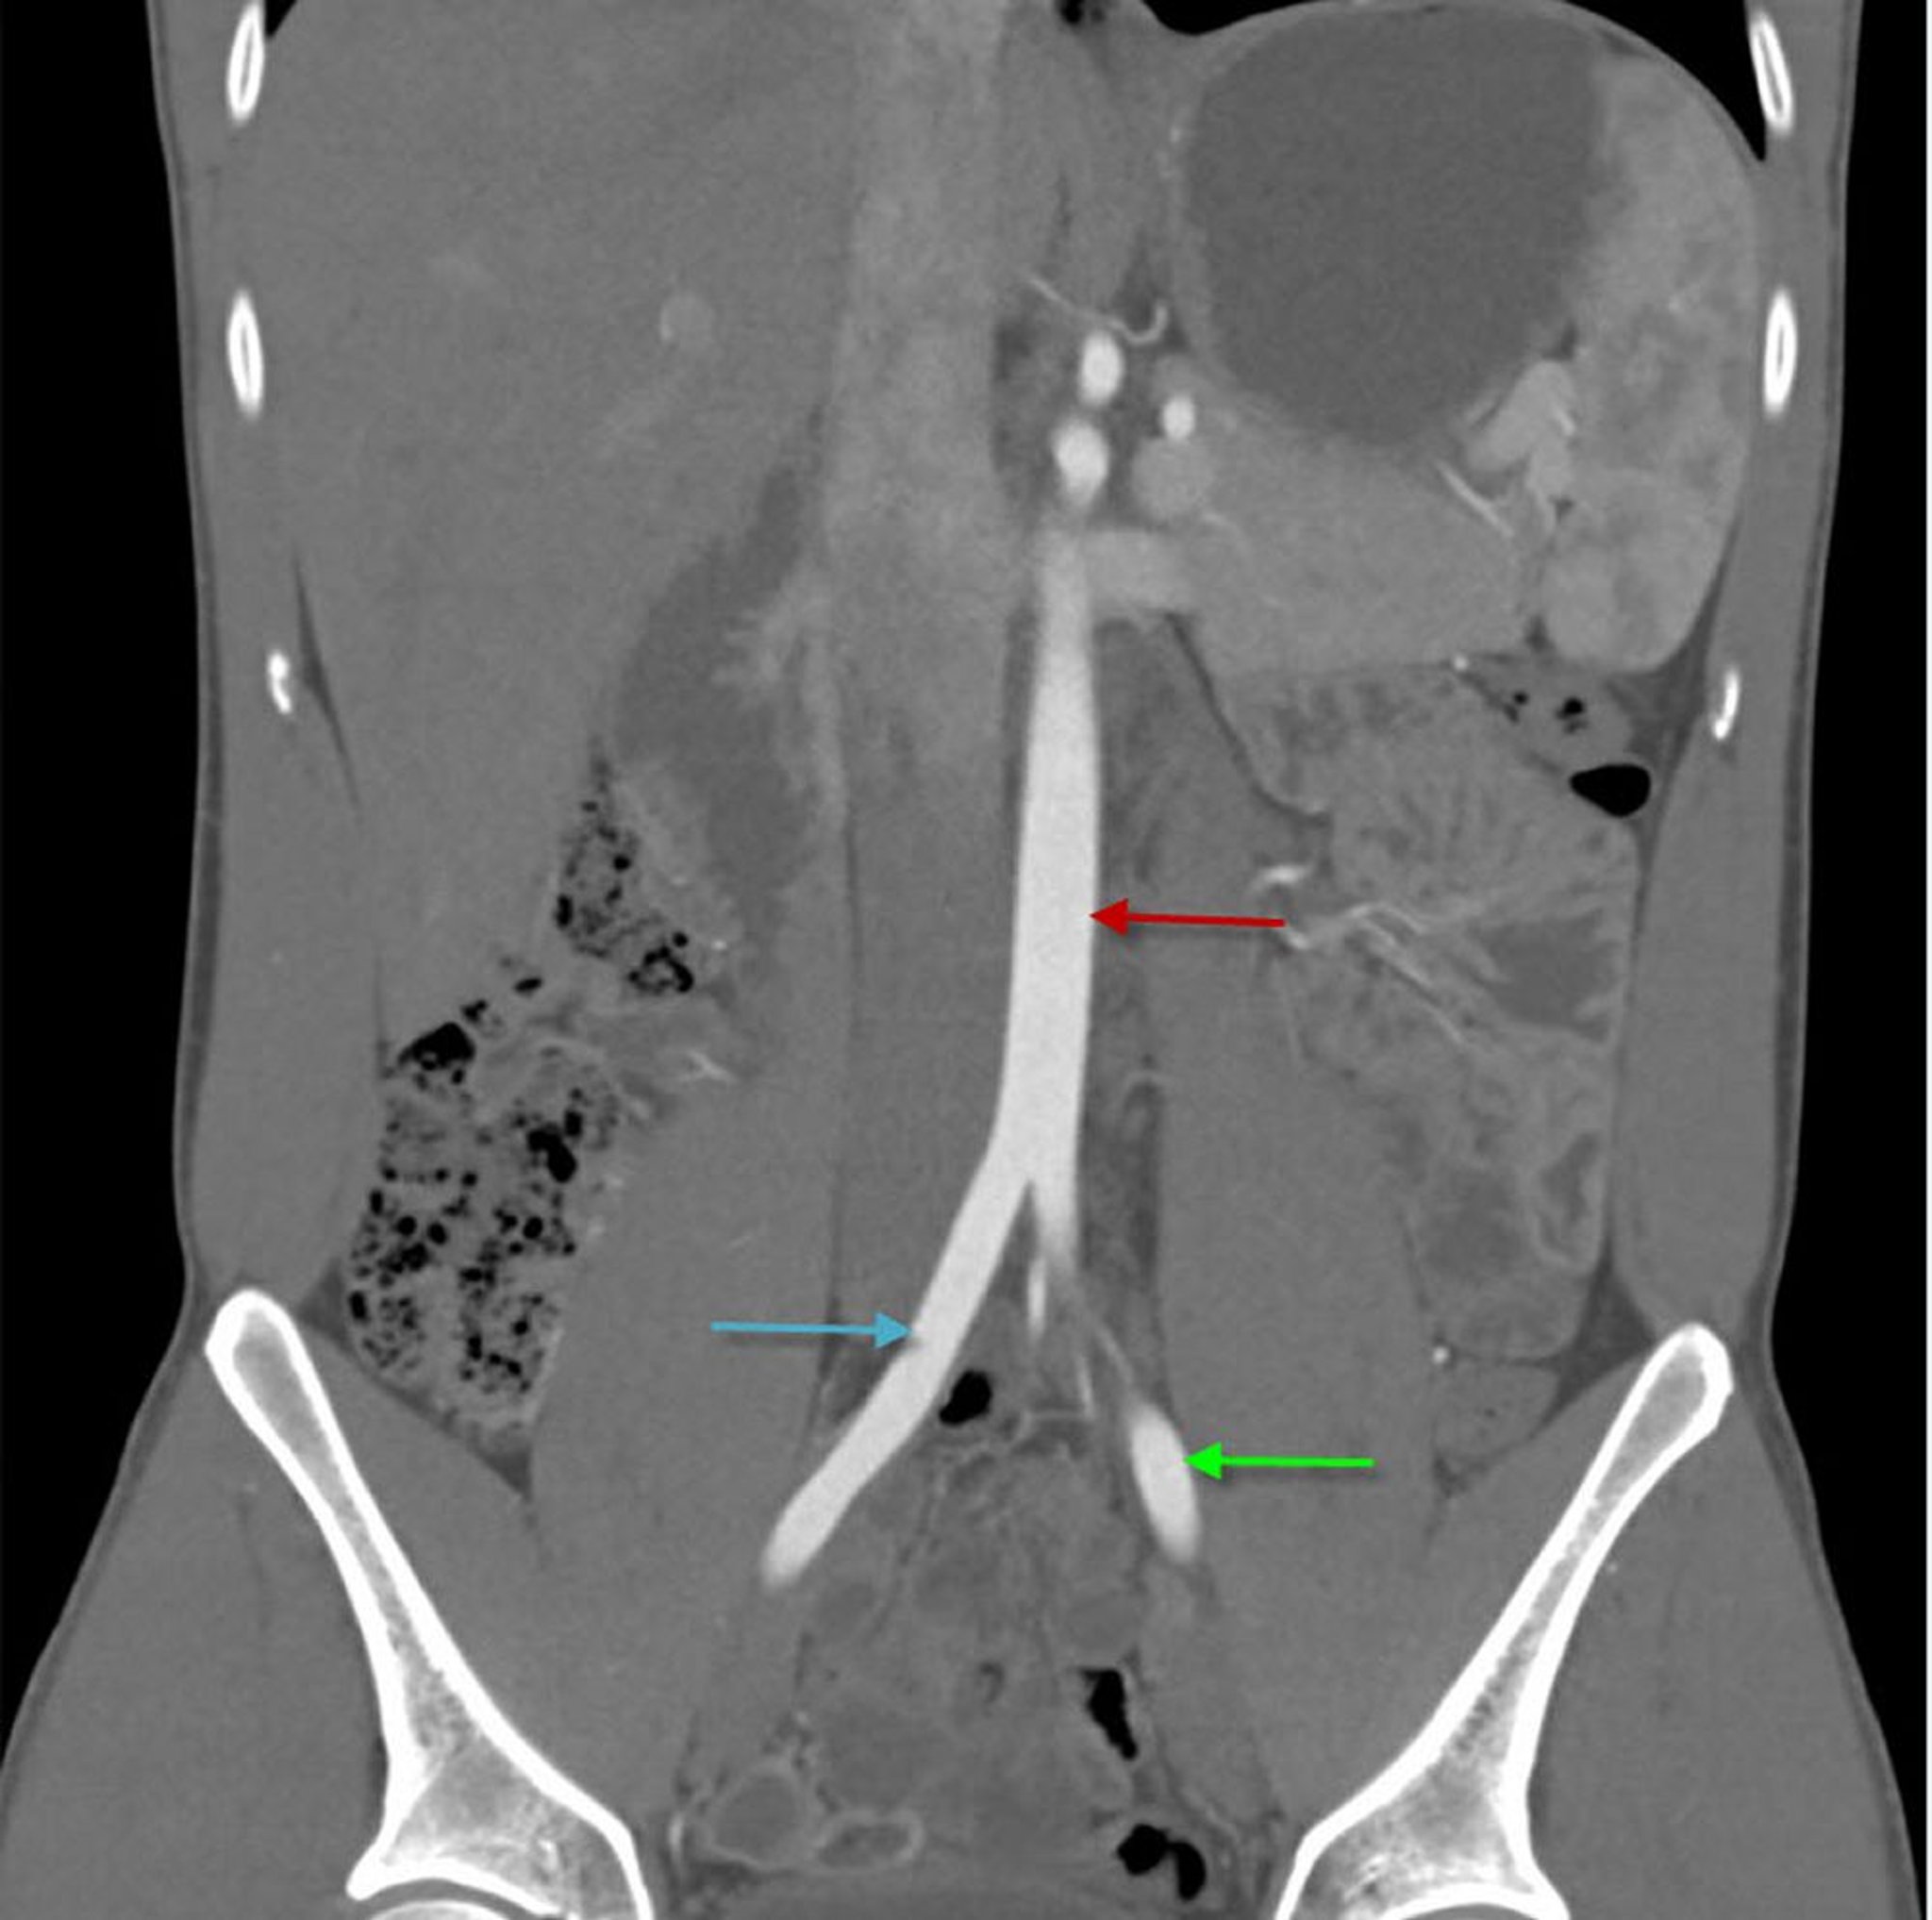

Angio-TDM (vue coronale) de l'abdomen montrant l'aorte abdominale

Cette image montre l'aorte abdominale (flèche rouge) se divisant en artères iliaques communes droite (flèche bleue) et gauche (flèche verte).